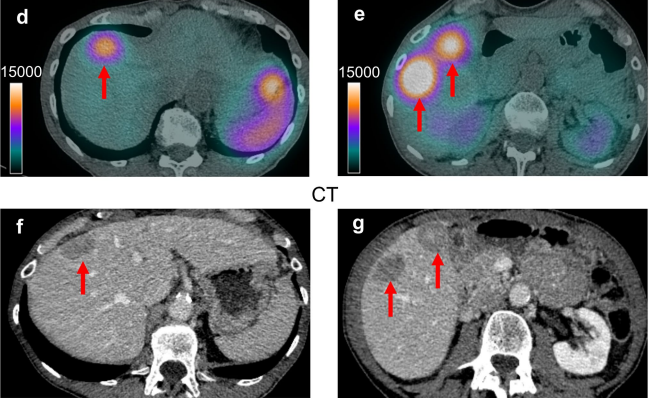

Read the full report by clicking here Notes from Ronny. Some people are calling this ‘beta plus’ indicating it’s more advanced than regular beta emitter PRRT out there. But other sources suggest this is a new form of PRRT to compete with beta-emitter (e.g. Lu177 Lutathera) and alpha-emitter versions currently in clinical trials (225AC and 212Pb versions). What is the plus? What makes it beta plus is auger electrons. These are tiny particles of energy released when certain radioactive medicines break down inside a cell. They are much weaker and shorter‑ranged than the “beta particles” used in standard PRRT. i.e. instead of travelling millimetres, they only move a few nanometres (that’s smaller than the width of DNA). Why that matters Because they don’t travel far, Auger electrons only cause damage right where they are released. If the radioactive medicine gets close to the cell’s DNA, Auger electrons can cause very precise damage, making it harder for the cancer cell to repair itself. Unlike beta particles, they don’t “spill over” into nearby healthy tissue — they’re more like a scalpel than a shotgun. i.e. it’s more targeted than current PRRT treatment. Update 14th March 2024 – First-in-human administration of terbium-161-labelled somatostatin receptor subtype 2 antagonist ([161Tb]Tb-DOTA-LM3) in a patient with a metastatic neuroendocrine tumour of the ileum Here, the Basel sponsor reports on the first patient (78-year-old man) with a metastatic, hormone-active (carcinoid syndrome) ileal neuroendocrine tumour (G1, Ki-67, < 3%), who received a test infusion of 1 GBq [161Tb]Tb-DOTA-LM3 in an ongoing prospective Phase 0 study. So far, the patient received long-acting octreotide, which was stopped 2 months

A new clinical trial being conducted at a single centre in Switzerland aims to explore a therapy using a novel somatostatin receptor subtype 2 antagonist labelled with Terbium-161 (161Tb-DOTA-LM3). The study is sponsored by University Hospital, Basel, in collaboration with the Swiss National Science Foundation and the Paul Sherrer Institute and builds upon research funded by NET Research Foundation (NETRF). The goal of the proof-of-concept study is to measure the therapeutic index of 161Tb-DOTA-LM3 in comparison to the current standard treatment with 177Lu-DOTATOC in gastroenteropancreatic neuroendocrine tumours (GEP-NET). Damian Wild, MD, PhD, leads the current proof-of-concept trial at University Hospital, Basel. The study will enrol up to 16 patients who have metastasized and non-secreting GEP-NETs (grade 1 and 2). Patients will be randomized into two treatment groups. In the first phase of the study, one test injection with 161Tb-DOTA-LM3 and 177Lu-DOTATOC will be administered in both randomized groups in a different order, followed by approximately 3 cycles of PRRT in both groups. In the second phase, two test injections with 161Tb-DOTA-LM3 with different peptide amounts will be administered in both treatment groups in a different order, followed by approximately two cycles of PRRT with 161Tb-DOTA-LM3. Additional information on the study can be found at the link below. Interested participants should talk to their treatment team about eligibility and determine if the study is aligned with their treatment goals. I also draw your attention to the inclusion and exclusion criteria in the clinical trials document linked below.